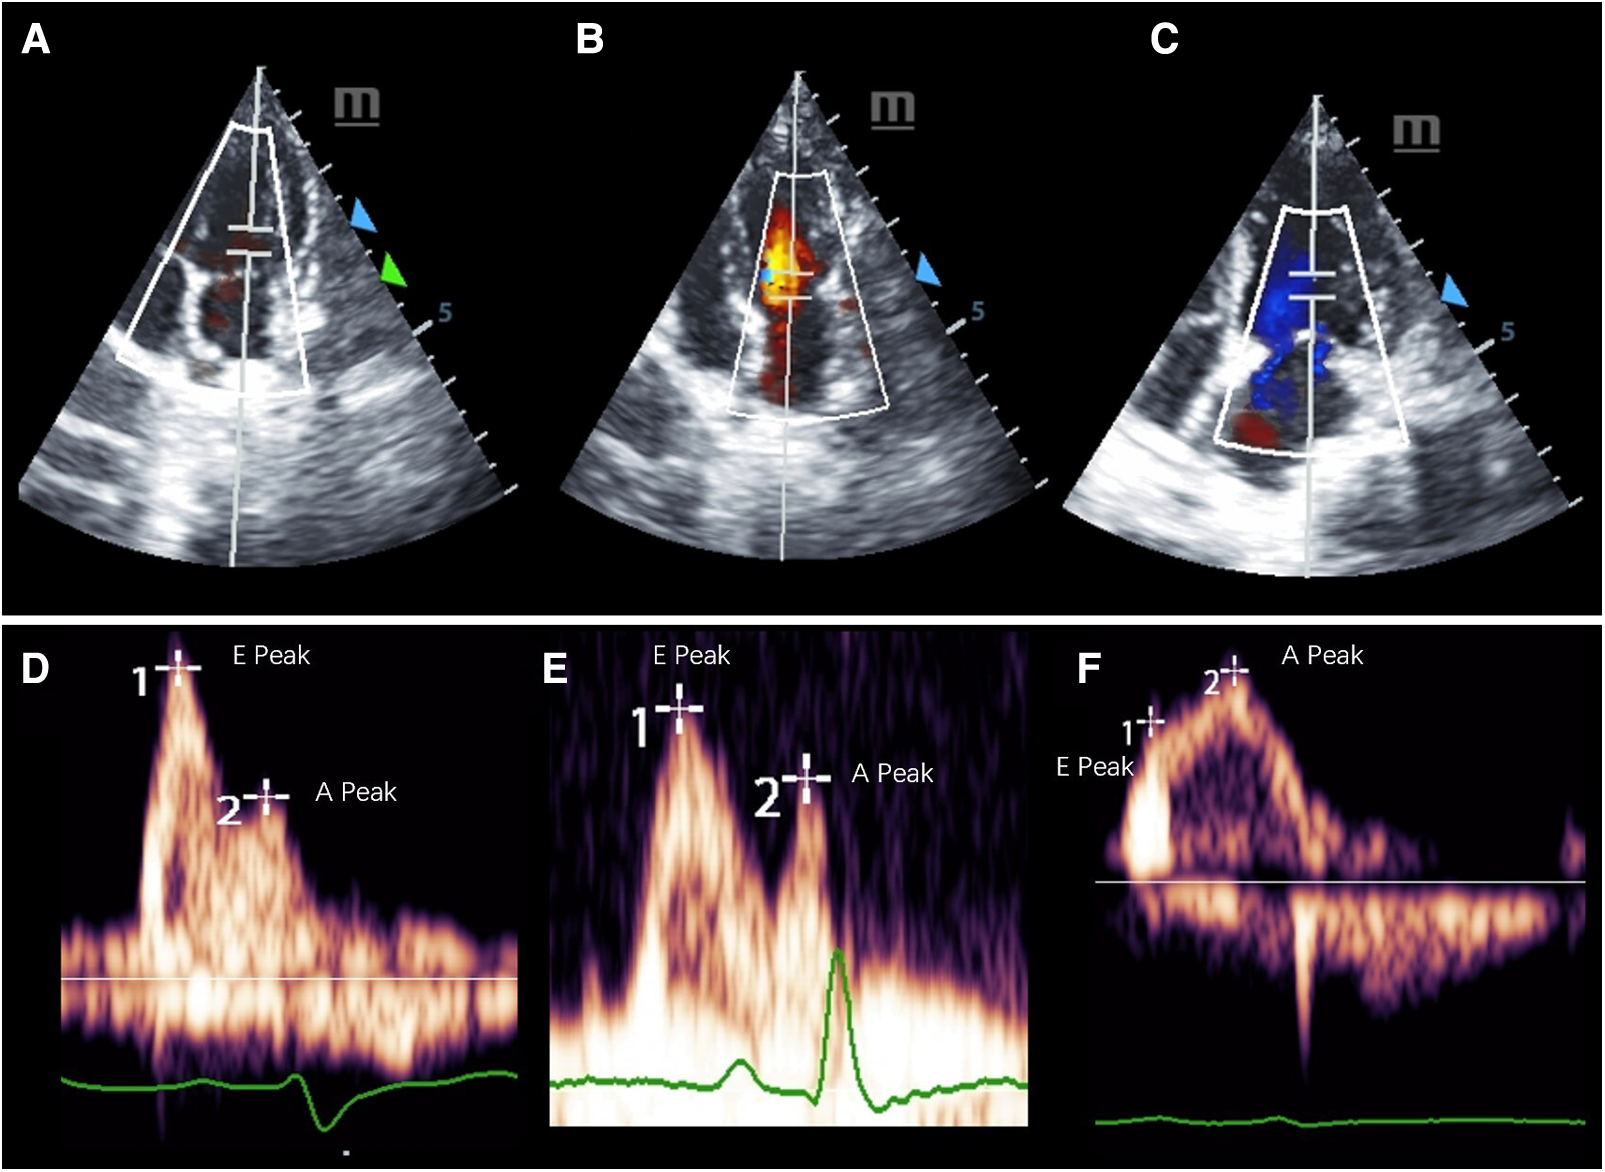

M-mode Doppler ultrasound was used to measure the left ventricular contractile capacity. There was no significant difference in LVEF between the healthy control and the HFpEF groups. However, the LVEF value of the HFrEF group decreased significantly, which was similar to that of human patients with systolic dysfunction. A decreasing E′/A′ or E/A ratio and low E′ velocity was the typical echocardiography finding with diastolic dysfunction (Table 3). Pulse Doppler for E, A peak measurement were shown in Figure 3.

Figure 3

Representative pulsed-wave Doppler images of mitral inflow in three groups of cynomolgus monkeys. (A–C) shows the measurement location and the (E,F) display the E and A peaks of each group.